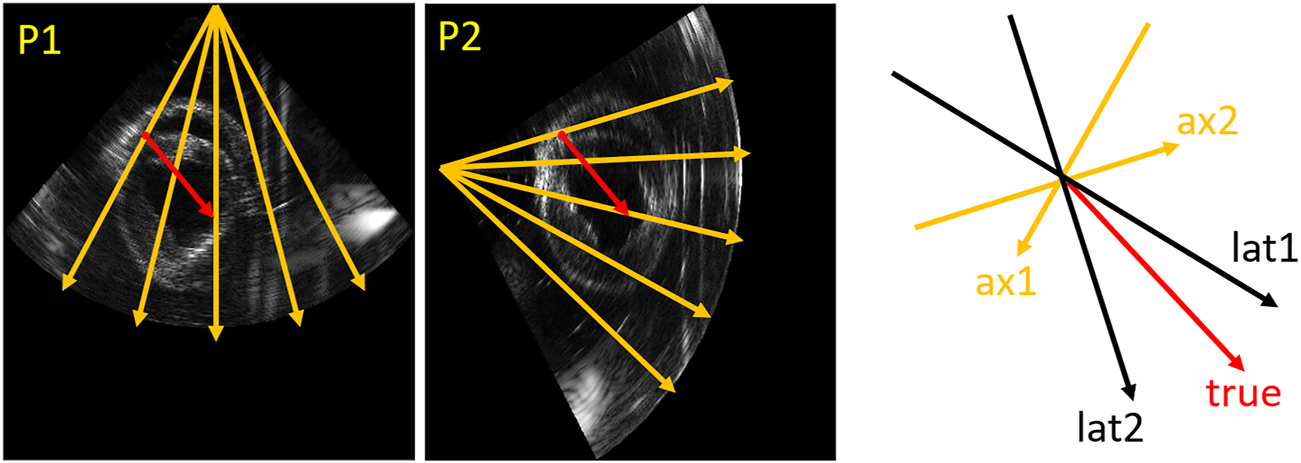

As Figure 4 shows, the true direction of the red point in the tracking mesh is decomposed into the axial and lateral directions. Therefore, the estimated true displacement can be represented using unit axial vectors and axial displacements of the dual probes:where and are the unit axial vectors of the two probes. and are the estimated true displacements in Cartesian coordinates. and are the axial displacements measured by the two probes.

FIGURE 4

Vector representation. An example (relative angle 75°) in the tracking mesh is shown (red point), where orange (ax1, ax2), black (lat1 and lat2) and red (true) arrows represent axial, lateral and true directions, respectively.

Since Eq. 2 consists of a system of two linear equations with two unknowns, a unique solution of the true displacement and can be estimated. Horizontal and vertical strain were calculated with respect to the initial configuration (Lagrangian frame of reference) by taking the spatial derivative of the derived displacement fields ( and ) in the horizontal (x) and vertical (y) directions using a 2-D least-squares strain estimator (2DLSQE) with a fixed size of 5 by 9 pixels [40]. The resulting horizontal and vertical strain were converted to radial and circumferential strain using the following equations [41]:where is the angle between the ultrasound beam and the radial strain. , and represent horizontal, vertical and shear strain in Cartesian coordinates respectively. and are the resulting radial and circumferential strain.